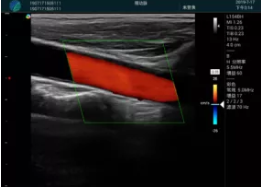

可視化甲狀腺穿刺引導(dǎo)

頸動脈血流充盈飽滿,無外溢

肝內(nèi)血管顯示清晰,血流敏感無外溢